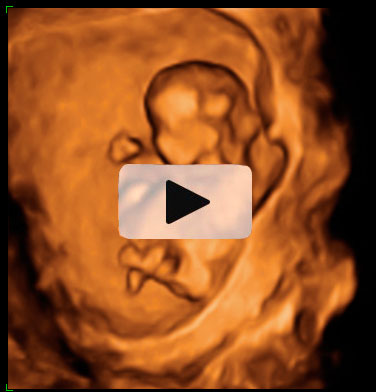

Ecografía 4D semana 12: Bebé moviendo brazos y piernas

La ecografía 4D muestra un bebé de 12 semanas de gestación moviéndose con gran vitalidad dentro del útero materno. Se percibe perfectamente que el feto tiene formadas todas sus estructuras básicas, a falta de que maduren a lo largo del embarazo.

Ecografía en 4D de bebé de 12 semanas moviendo brazos y piernas

La vitalidad del bebé es increíble. Mueve brazos y piernas con energía, como si estuviera nadando, o haciendo un "sprint" final. En realidad está apoyado en la pared uterina de su madre. Se perciben las estructuras básicas del feto con gran claridad: cabeza, aún muy grande respecto al cuerpo, tronco y extremidades. Este movimiento es uno de los signos de vitalidad fetal que los ecografistas siempre evalúan en sus exploraciones.